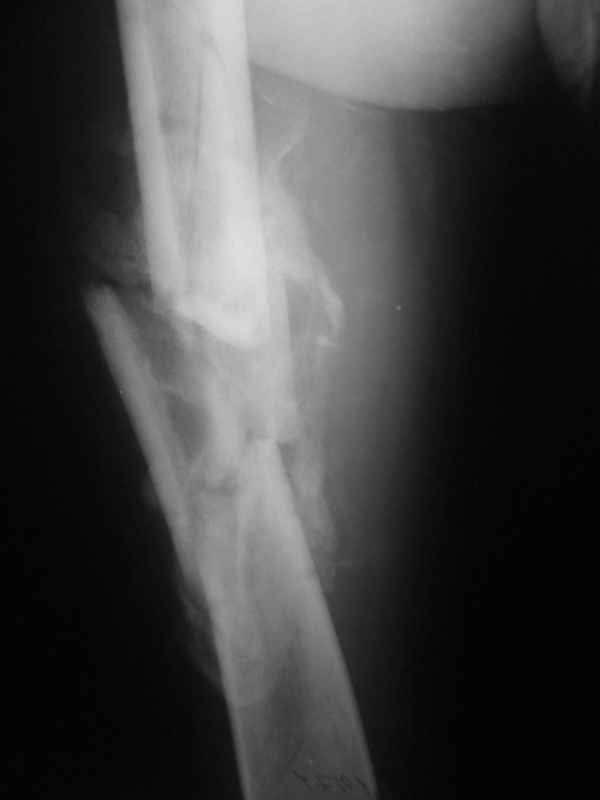

Вы думаете, что в данной ситуации возможна закрытая мобилизация?

Попробовать-то можно. И просто руками "об колено", а то и наложить аппарат, приложить флексионные и ротационые усилия прямо за разъединенные секции.

Если уж никак, то сделать чрескожную остеотомию.

Но если картинки недавние, IMHO должно получиться закрыто разобщить.